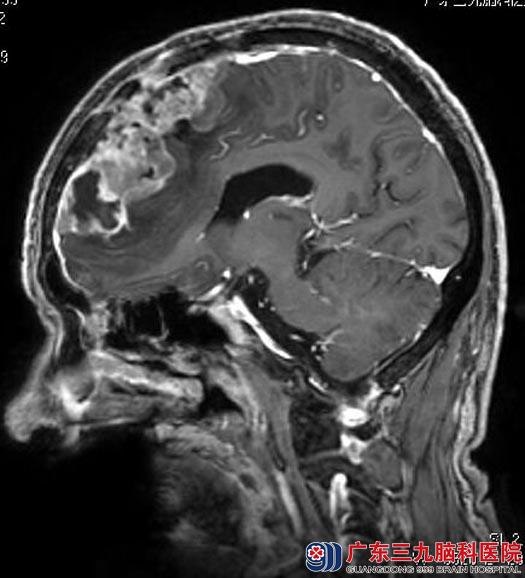

广东三九脑科医院头颅MR检查提示:拟额部脑膜瘤术后复发,大小约6.24cm×4.54cm×8.54cm,邻近脑膜示线样明显强化,跨越中线向对侧生长,相应部位额骨受累及。

完善各项术前准备后,由鲁明主任主刀,在全麻下行双侧额部巨大复发脑膜瘤切除术,术前导航定位肿瘤体表范围,术中显微镜下见肿瘤呈红色,质韧、血供丰富,边界清,镜下行肿瘤切除,手术顺利。术后杨先生的语言、肢体活动正常,已康复出院。病理结果:非典型脑膜瘤(WHO II级)。